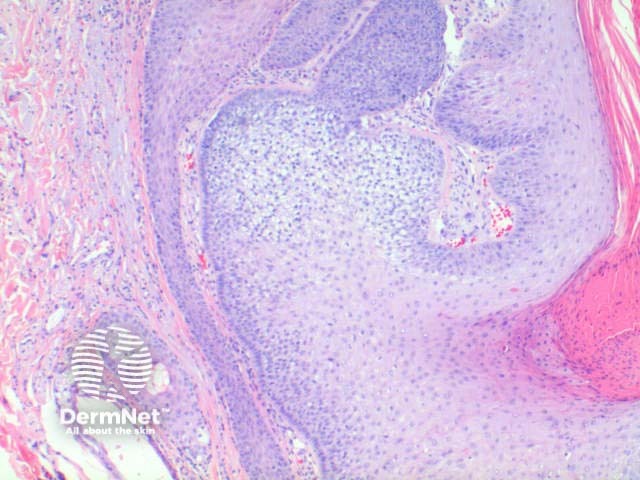

Trichilemmoma is usually a symmetrical epithelial nodular proliferation. Figure 1. There may be mild papillomatosis with overlying hyperkeratosis. Figure 2. The key finding is of a downgrowth of epithelial cells with increasing clear cell differentiation. Figure 2, Figure 3. These changes are frequently more obvious towards the base of the lesion. The clear cell is PAS positive but diastase labile indicative of the glycogen contents. There is often basal peripheral palisading, resting on a distinctive PASD positive eosinophilic hyaline basement membrane. Figure 4.

Figure 2